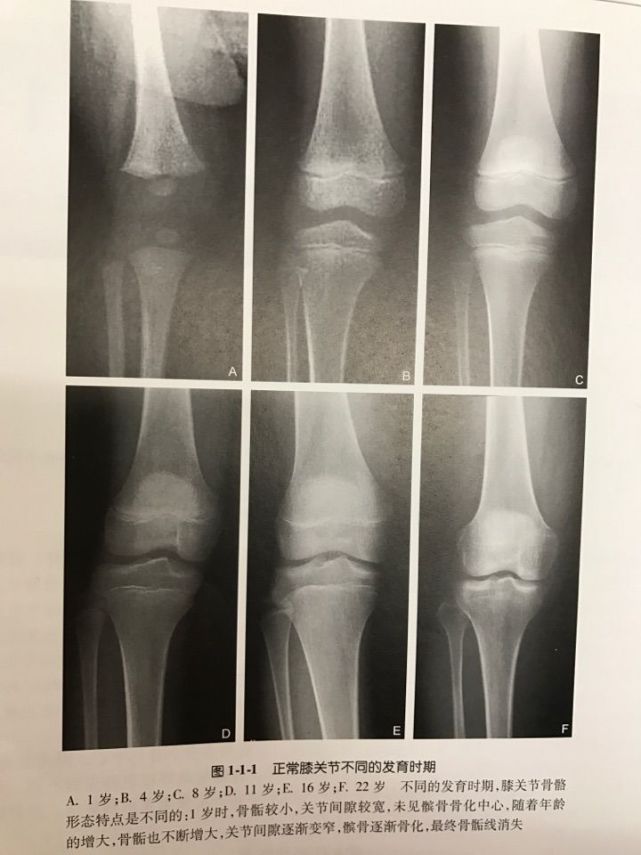

最近看到图谱突然想到这个问题,原本的解释是有问题的,婴幼儿的髌骨未骨化,膝关节也未发育完全,所以跪着不疼